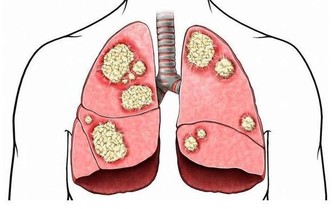

近年來,胰腺癌的發病人數也不容小覷,而且大約有一半的新增患者年齡都在60歲以上。胰腺癌非常難被治愈,5年生存率小於1%,所以在醫學上被稱為“癌症之王”。

胰腺癌的常見症狀包括背痛、胃痛、體重異常減輕等,最為明顯的跡像是皮膚和眼白開始泛黃。另外,一個不容忽視的事實是,有超過30%的胰腺癌患者在確診患上這種惡性腫瘤前,被診斷出2型糖尿病。醫生認為,這可能是胰腺腫瘤干擾了胰島素分泌的結果,才會導致出現糖尿病。

如果發現自己的身體出現了這些異常症狀,一定要及時尋求醫療幫助。